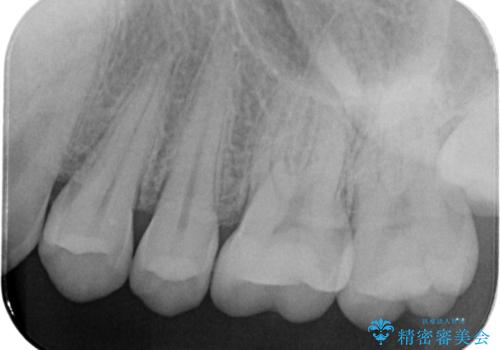

- 金属アレルギーが気になるとの事で来院。

拡大鏡下で銀歯を外し、セラミックの詰め物で修復しました。

適合の良い詰め物が入りました。